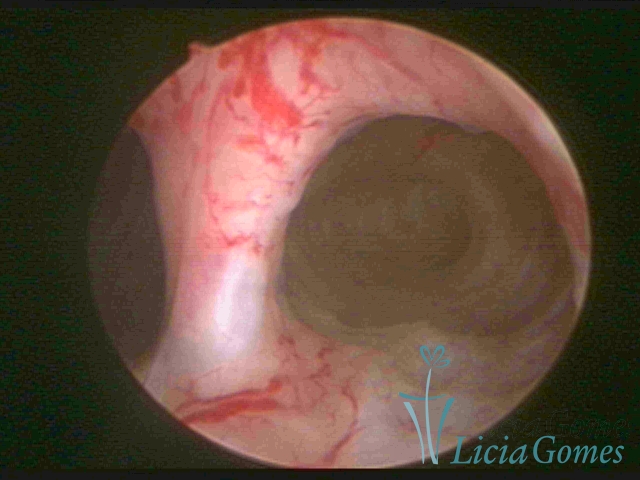

Septate uterus

It probably occurs by the lack of resorption on the middle line, in the merge of Müllerian ducts. The uterus is divided by a partial or total septum which is viewed as a crossbar, not covered by endometrium, which not bleeds when sectioned.

Complete septum when it occupies the whole extension of the cavity, dividing it into two hemicavities.

When this septum occupies only a part of the extension of the uterine cavity, it is considered as incomplete.